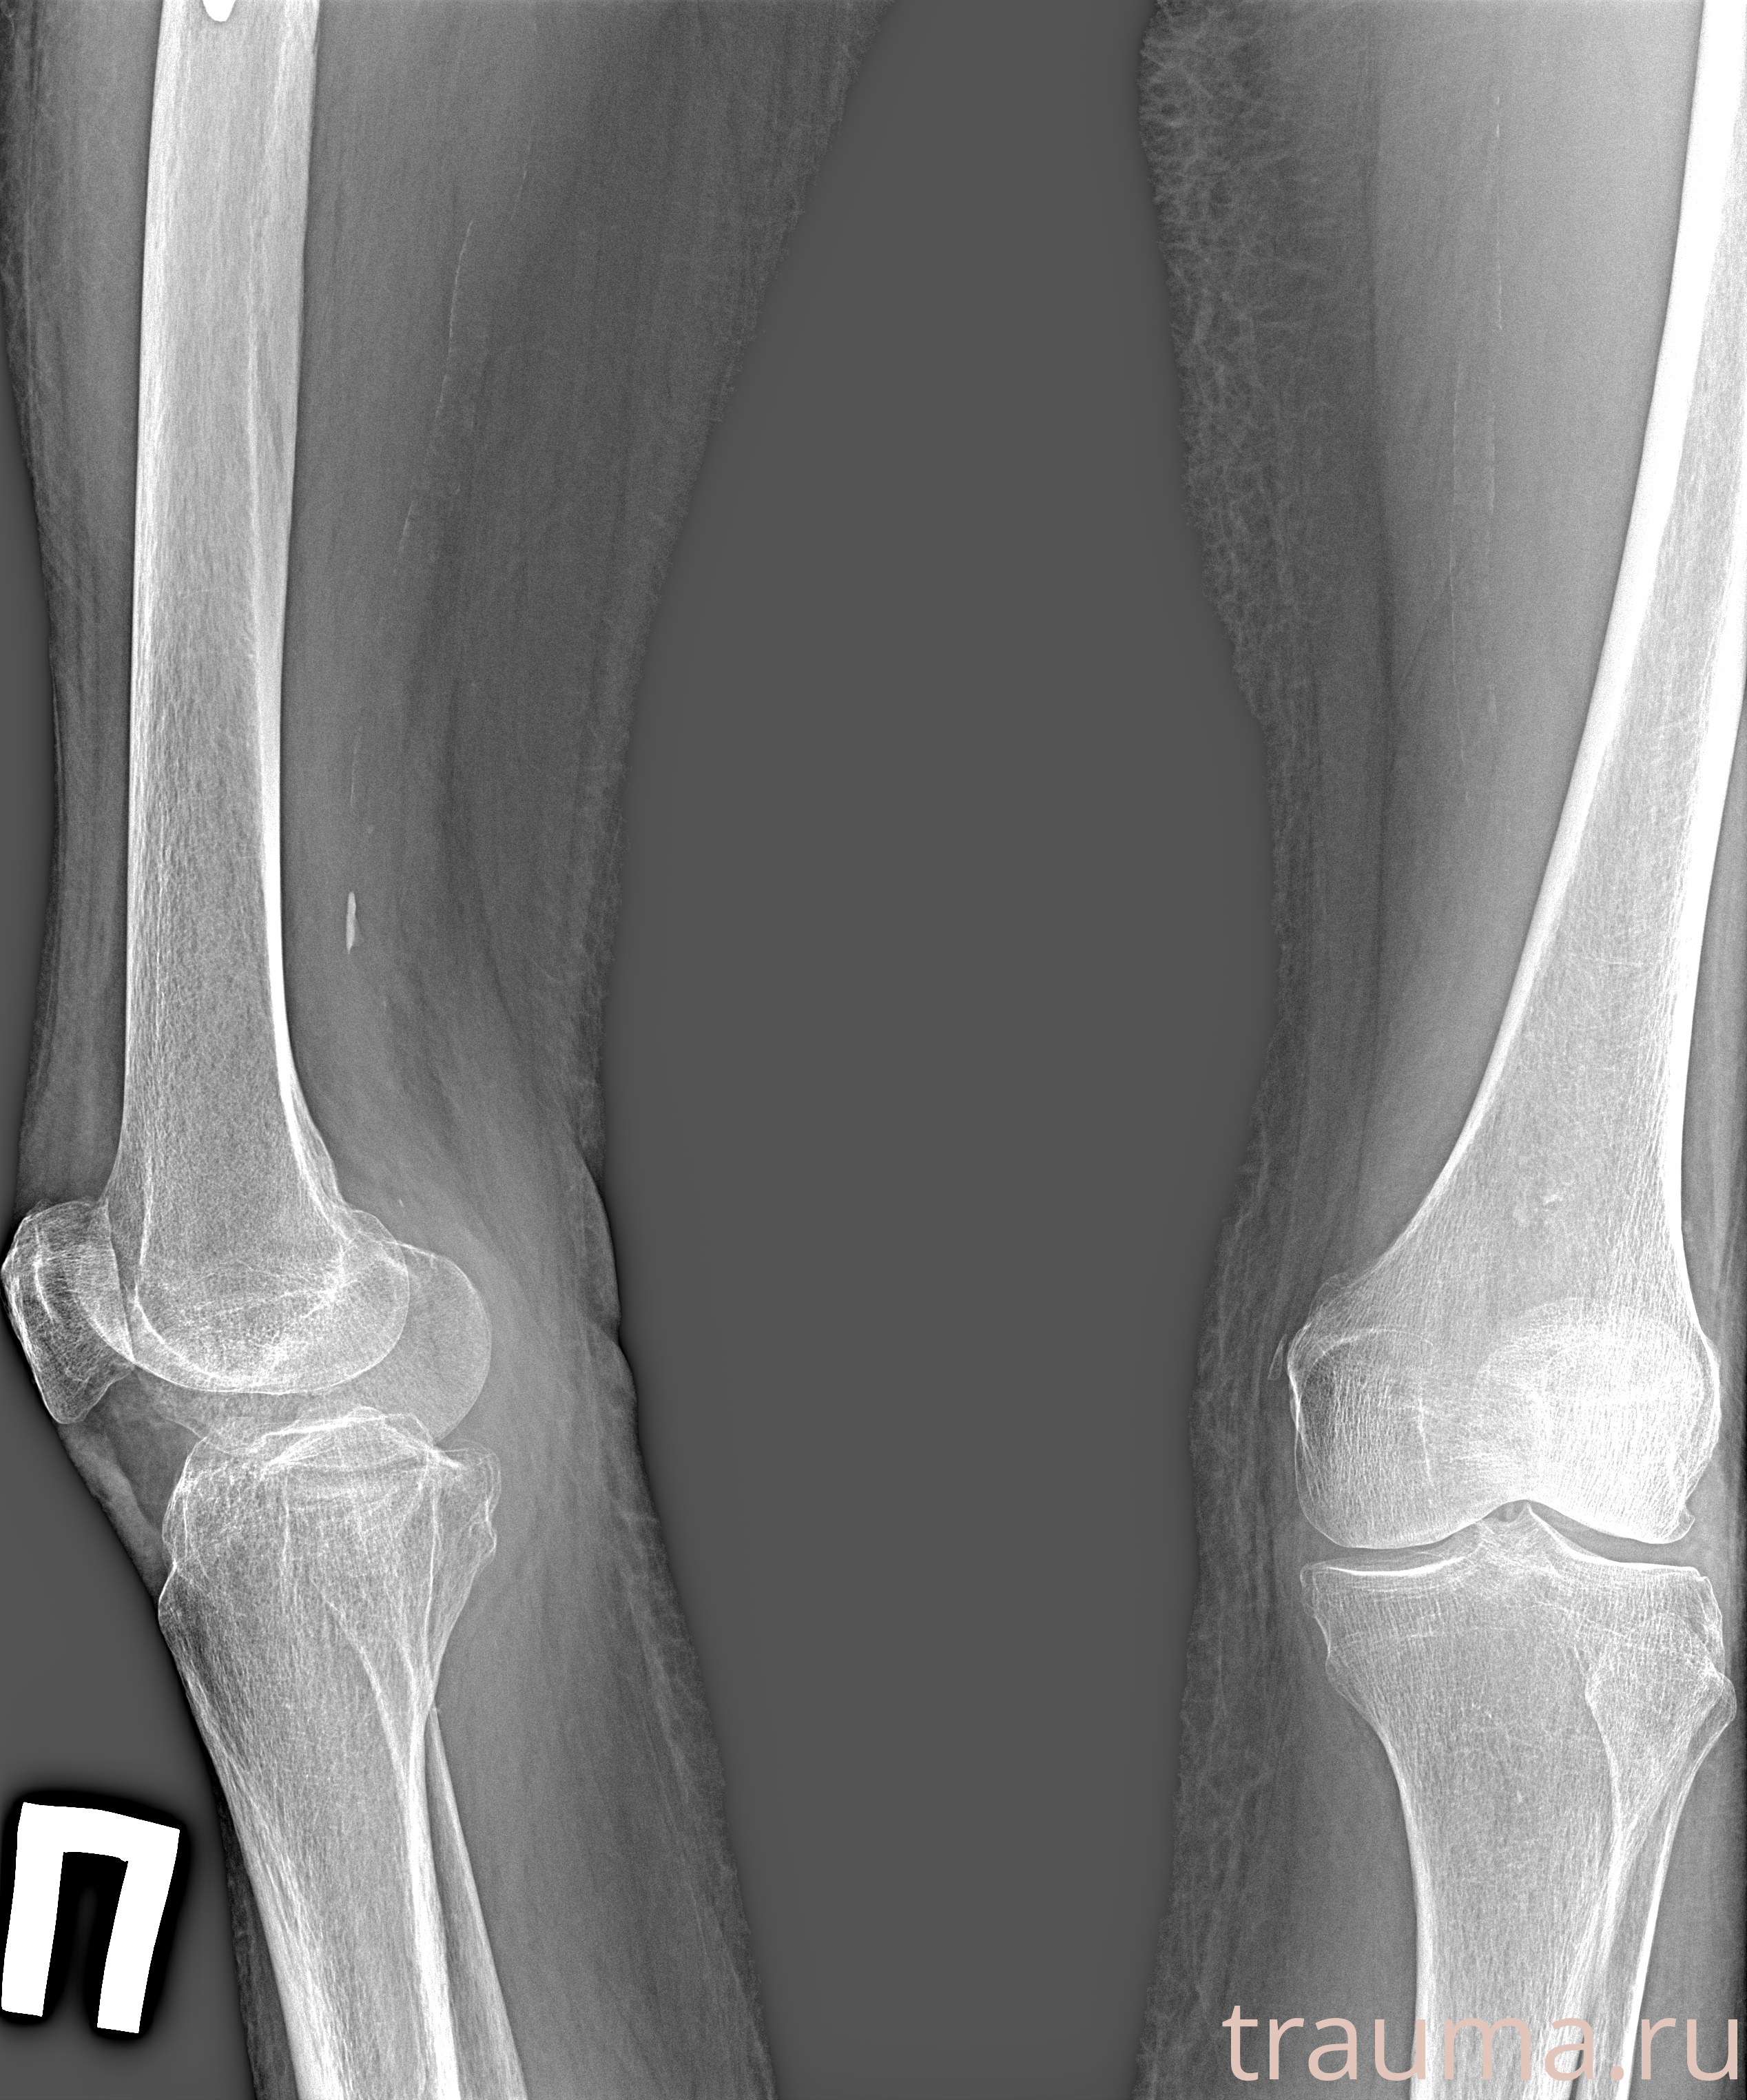

Рентген на дому: по вашему адресу приезжает врач-рентгенолог, травматолог-ортопед с мобильным рентгеновским аппаратом, проводит диагностику травмы или заболевания, делает необходимые рентгенограммы, дает рекомендации по дальнейшему лечению. Получить качественные снимки в домашних условиях возможно благодаря уникальной методике, разработанной МосРентген Центром для института  Склифосовского